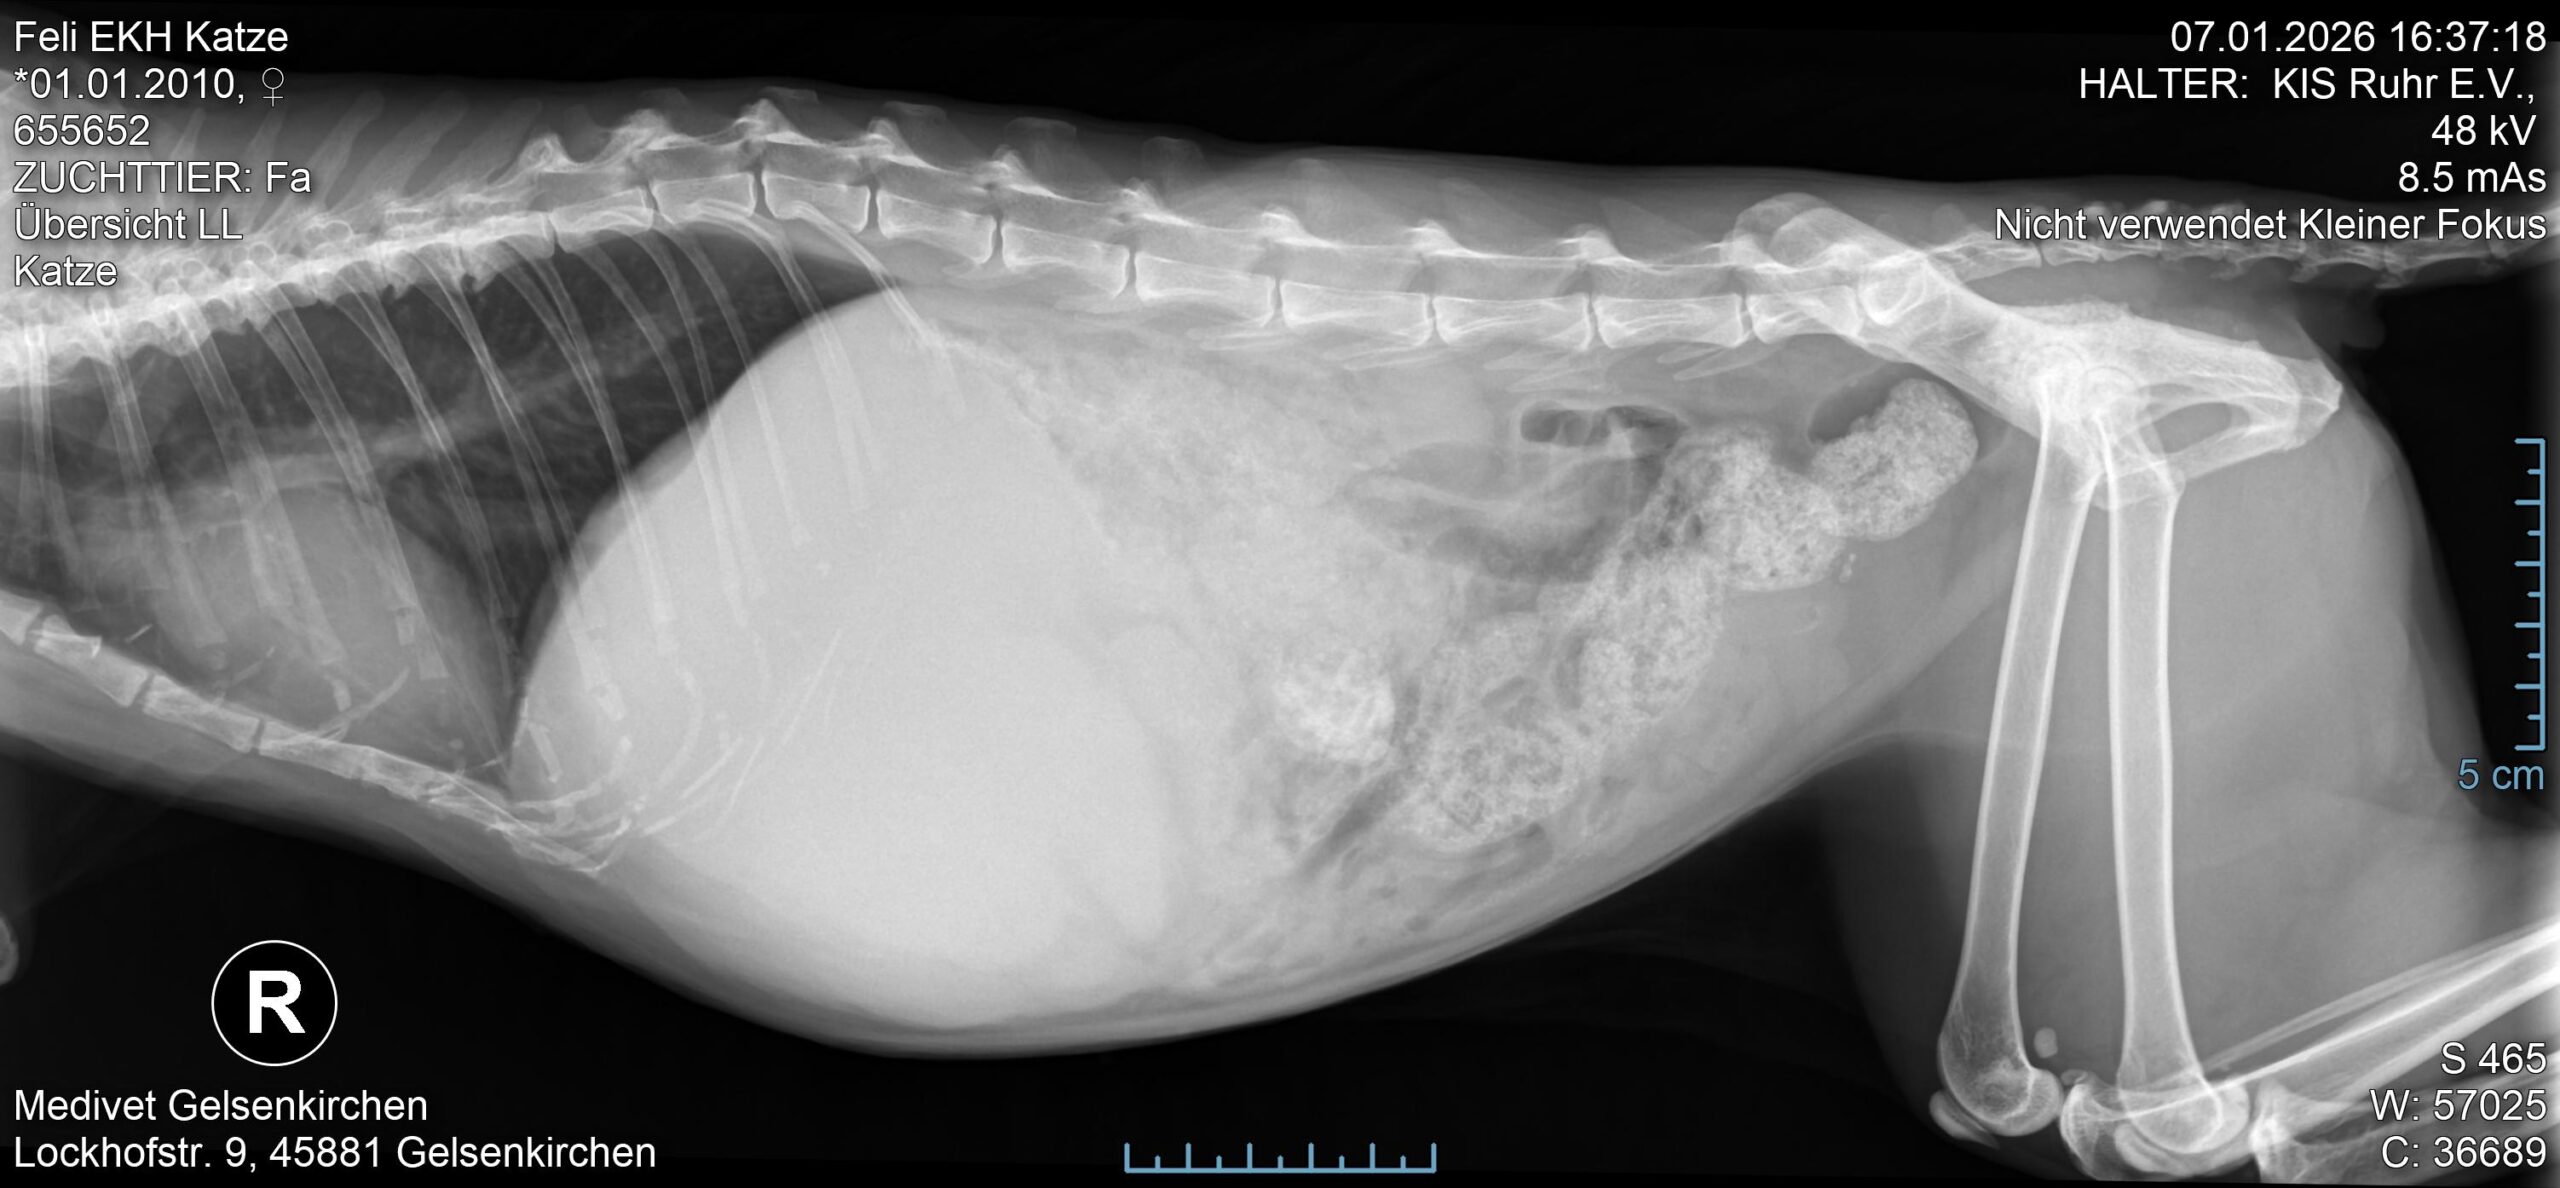

Die Ärztin fand den riesigen Lebertumor sofort. Ebenso hatte Feli erwartungsgemäß Spondylosen, ein Herzgeräusch und vermutlich kaputte Nieren.